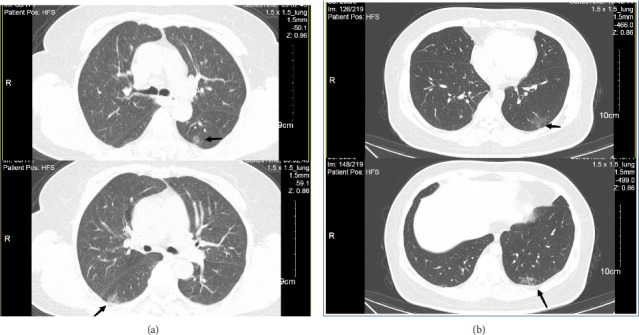

Background: Since the SARS-CoV-2 pandemic, many patients have suffered prolonged complications, called "long COVID." Mycoplasma pneumoniae is a common respiratory pathogen. Reports of simultaneous long COVID and M. pneumoniae infections are rare in the literature. Methods: We analyzed the clinical data of patients with long COVID-19 who visited the Respiratory Clinic of The Affiliated Hospital of Hangzhou Normal University between January 1 and January 31, 2023, together with their laboratory and radiographic findings, with Pearson's χ 2 test. Results: Fifty-two patients diagnosed with both long COVID and M. pneumoniae infection and 77 with long COVID only were compared. The ages, clinical symptoms, and comorbidities of the two groups did not differ significantly (p > 0.05). However, sex and imaging findings differed between the groups. Conclusions: Our study showed that long COVID-M. pneumoniae coinfection was more commonly seen in females and patients with typical chest computed tomography (CT) images.